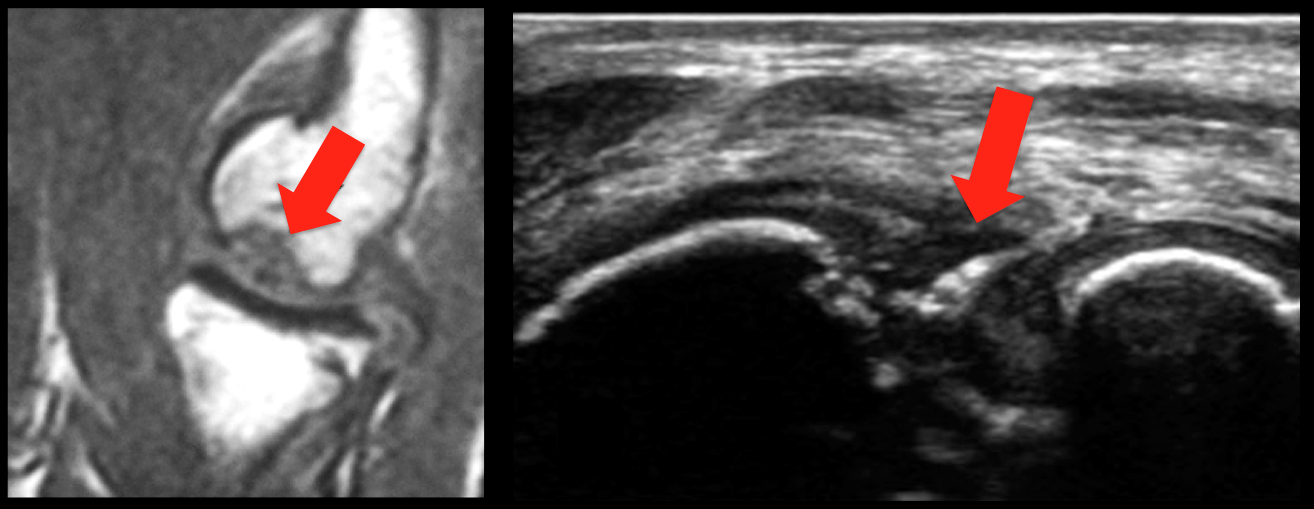

Elbow ultrasound of capitellar osteochondritis dissecans

Capitellar osteochondritis dissecans (COCD) typically occurs in adolescent athletes who are engaged in throwing sports that repetitively stress the immature capitellum, although the exact etiology remains unclear. The choice of treatment for COCD mainly depends on the patient’s age and characteristics of the lesion, including its size and fragment instability. Evaluating the stability of the osteochondral fragment is important when choosing surgical versus non-surgical treatment options. Stable lesions are more likely to heal with elbow rest, whereas surgery provides better results for unstable lesions. Preoperative assessment is based on clinical findings in combination with imaging results. The article of Yoshizuka et al. (2017) compared MRI and ultrasound (US). The US criteria in this study correctly matched the International Cartilage Repair Society classification in 23 of 24 patients. The sensitivity, specificity, positive predictive value, negative predictive value, and accuracy of the US diagnoses were 92%, 100%, 100%, 92%, and 96%, respectively. The outcome was that US achieved superior accuracy compared with MRI.